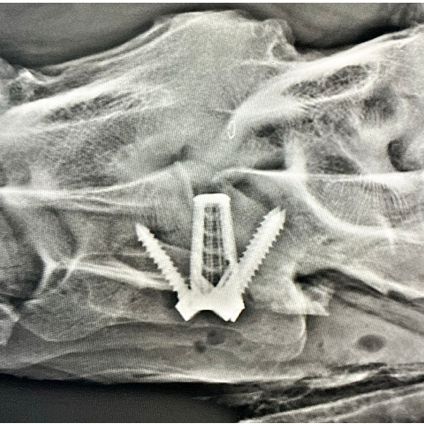

Die GPM ist stolz Dr. Fabrice Rossignol für die Networking Days 2026 (Tickets gibt's HIER!) als Referent ankündigen zu können. Mit seinen beiden Vorträgen "Cervical spine surgery – What is possible?" und "Upper airway surgery – Where are we headed?" berichtet er aus seinen beiden Spezialgebieten und bietet zum Thema Chirurgie an der Halswirbelsäule zudem mit Prof. Dr. Christoph Lischer (DipECVS, Pferdeklinik FU Berlin) noch einen ganztägigen Workshop an (In-depth session on cervical spine surgery incl. Wetlab demonstration).

Er ist an mehreren Forschungsprojekten zur Physiologie und Biomechanik des Kehlkopfs sowie zur Kehlkopf-Reinnervation beteiligt. Seit 2016 ist er zudem Mitglied und Vorsitzender der AOVET Large Animal Expert Group und Faculty und engagiert sich aktiv in der Entwicklung neuer orthopädischer Implantate.